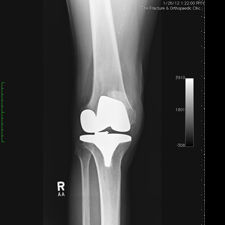

Bilateral Total Knee Replacement was recommended, and performed on July 27th 2011. Since surgery, the patient has made good progress and can now mobilize with the aid of a walker.

His x-rays and clinical examination suggest good early outcome with a fully mobilized patient with pain free knees and the ability to walk independently.

At the present time, he remains under our care and with physiotherapy and self-exercise, he will continue to improve.